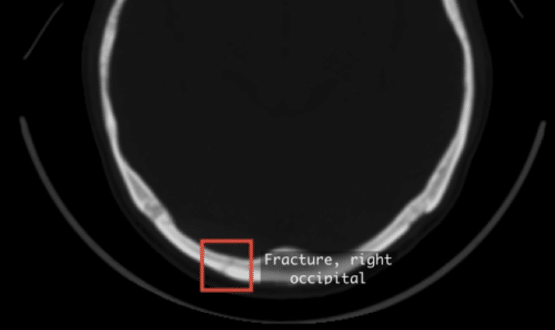

Blackford, the strategic AI platform and solutions provider, has partnered with Qure.ai, to deploy the neurocritical AI solution, qER, in